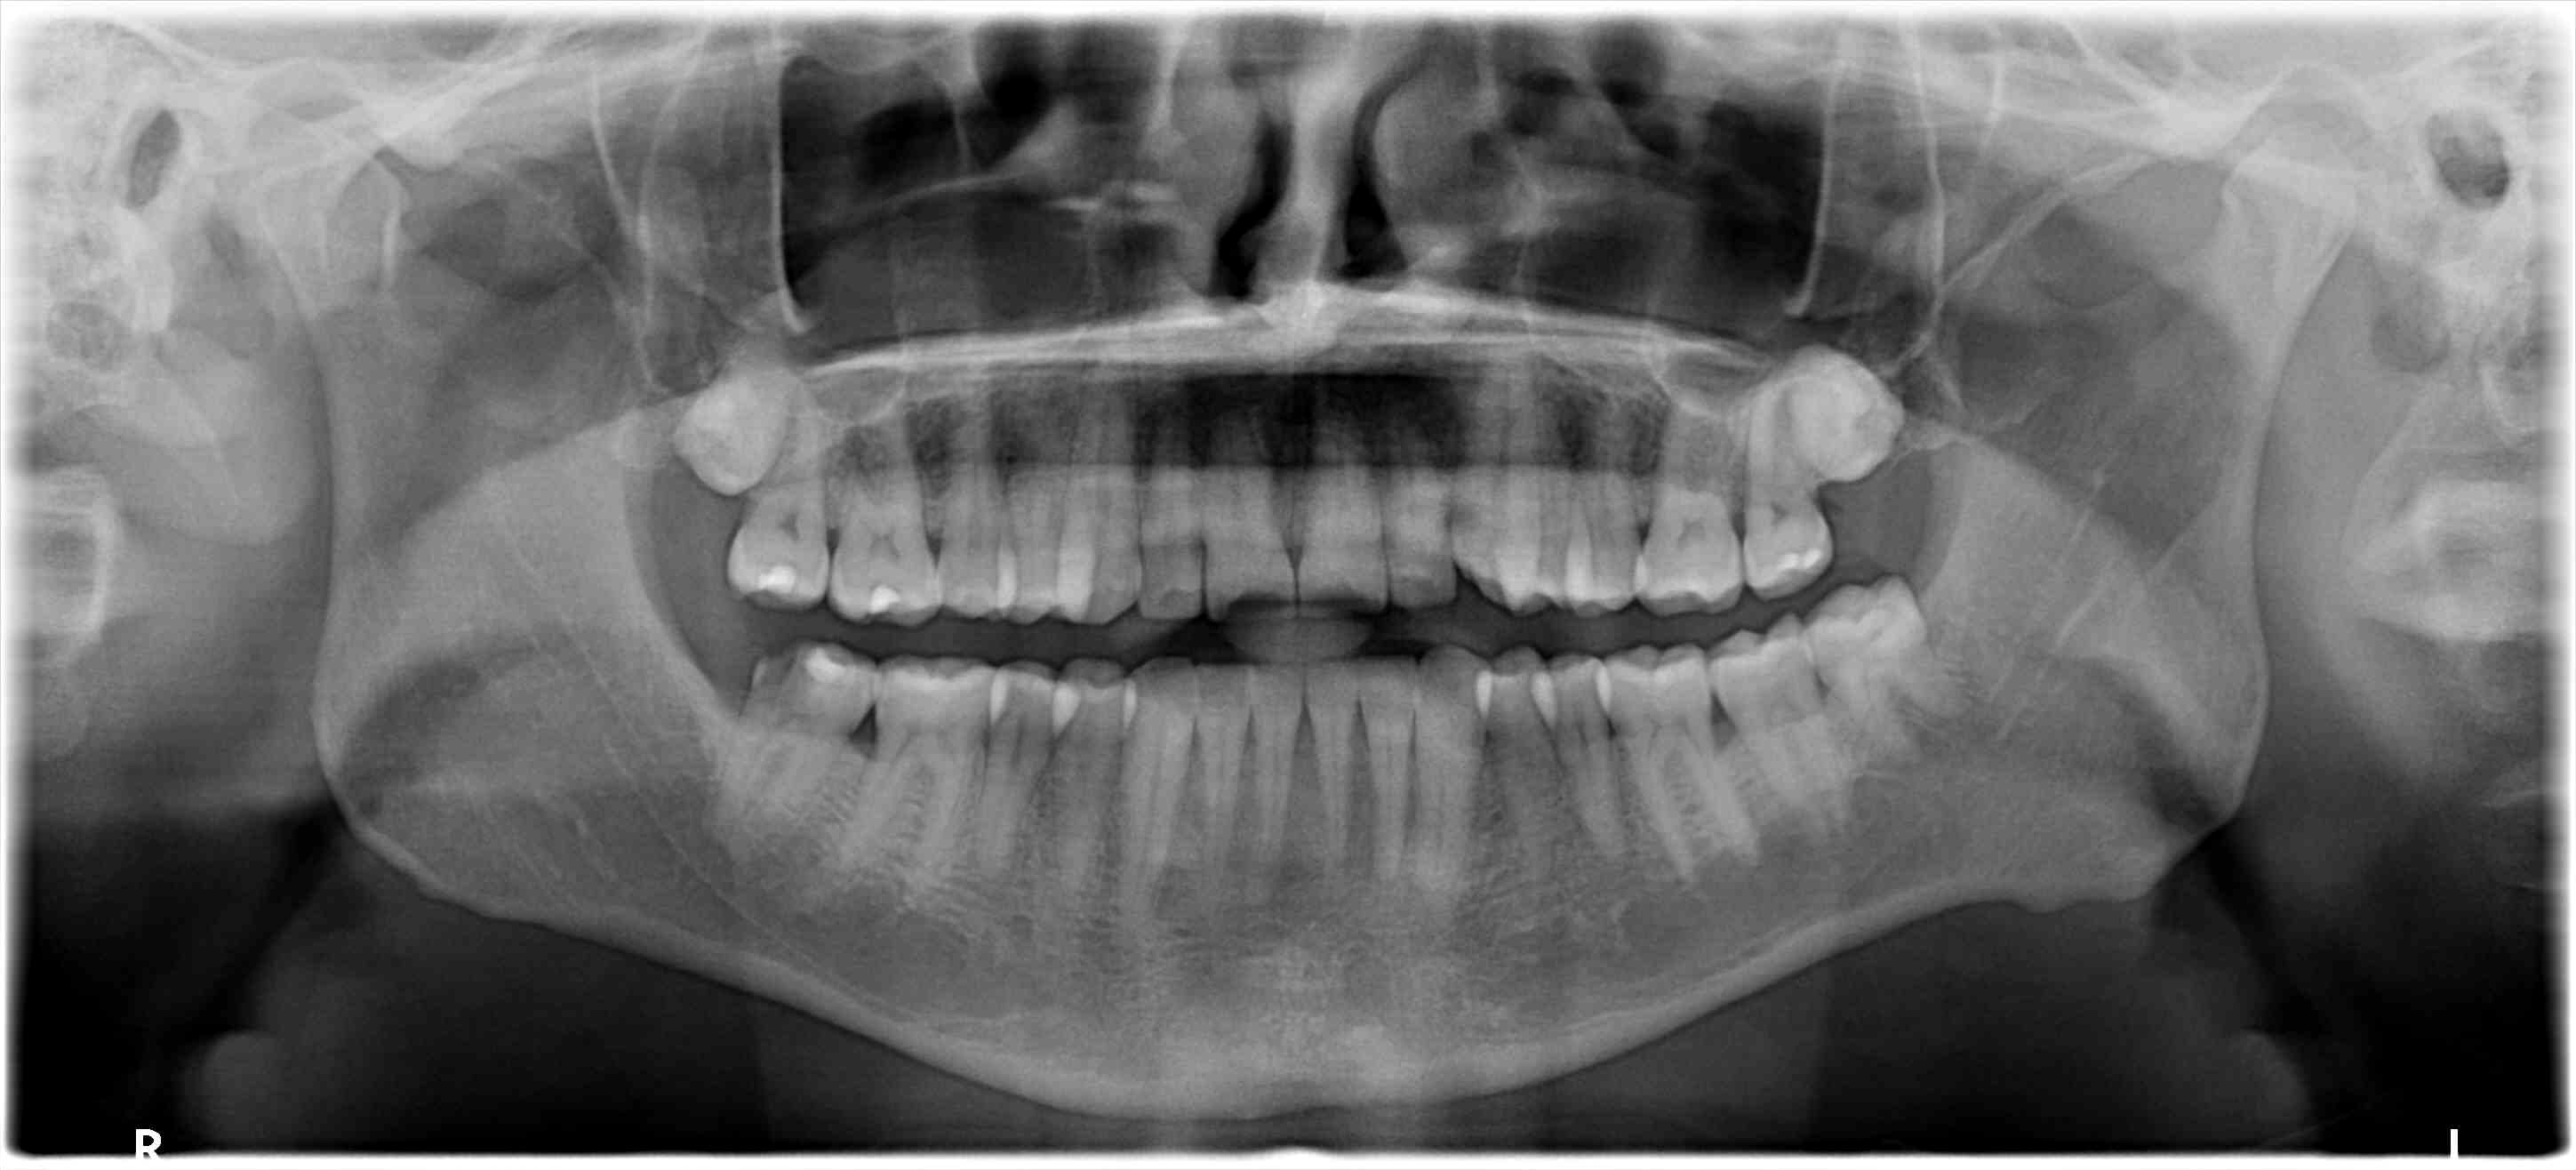

Diagnostic : Parodontite chronique apicale en phase aigue, il y a une semaine. Anesthesie impossible à ce moment la, mise sous AB depuis 5 jours. Au vu de la radio pre-op je considère le TR comme potentiellement compliqué.

Un gros canal Distal très excentré en vestibulaire est trouvé, ainsi qu'un fin canal MV relié au canal distal par un isthme peu profond. Je trouve également un fin canal ML. Les deux canaux mésiaux se situent bien en mesial, sur la même ligne parallèle au bord mesial et séparés de 1mm.

Parage canalaire des trois canaux à la LK 8/10/15/20 sur LT initial de 19mm et irrigation. ouverture du foramen avec gates. Aucun saignement.

Je vais tabler sur une morphologie en c (5 à 7% des 2e molaires mandibulaires) et une imagerie à la "burnax". Le plancher pulpaire ressemble au cas posté par Bill. Un c vestibulaire de distal à mv et un canal individualisé en ml. Dans ce cas le mv peut apparaître dans la furcation à la radio...